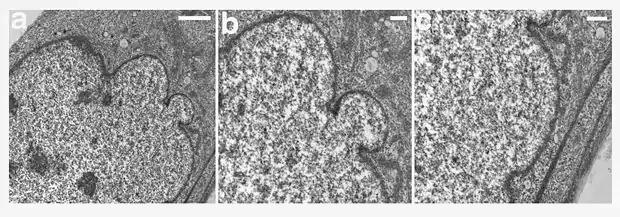

Мутации и вариации гена LMNA ассоциированы с мышечной дистрофией Эмери-Дрейфуса, семейной частичной липодистрофией, конечностно-поясной мышечной дистрофией, дилатационной кардиомиопатией, болезнью Шарко-Мари-Тута и синдромом прогерии Хатчинсона-Гилфорда. Синдром прогерии, исключительно редкое расстройство, вызывается синтезом ламина A неправильной формы, называемой прогерином.